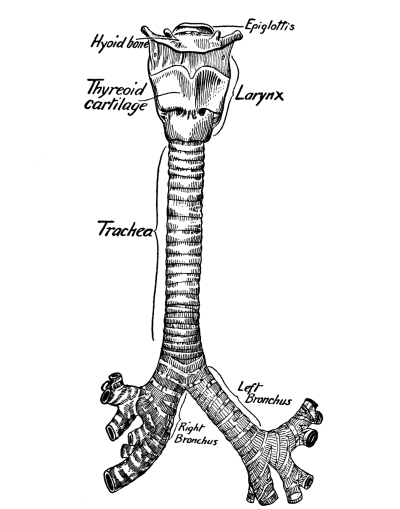

The Larynx, 121—The Trachea, 123—The Thyroid Gland, 124—The Thymus Gland, 124—The Bronchi, 125—The Lungs, 125—The Pleura, 125—The Mediastinum, 126—Respiration, 127—Air, 129—Respiratory Sounds, 129—Changes in Air in Lungs, 129—Effect of Respiration on Blood, 130—Nervous Mechanism of Respiration, 130—Variations in Respiration, 131. |

Cartilage consists of groups of nucleated cells in intercellular substance. It is very firm, yet highly elastic, and serves in the joints to break the force of concussion of the harder and less elastic bones. Except when it occurs at the end of a bone, it is covered with a membrane called the perichondrium, which carries its blood supply. In the nose, ear, larynx and trachea it serves to give shape, to keep the [Pg 17] passages open, and to afford attachment for muscles. Most of the skeleton of the fetus consists of cartilage, which later develops into bone.